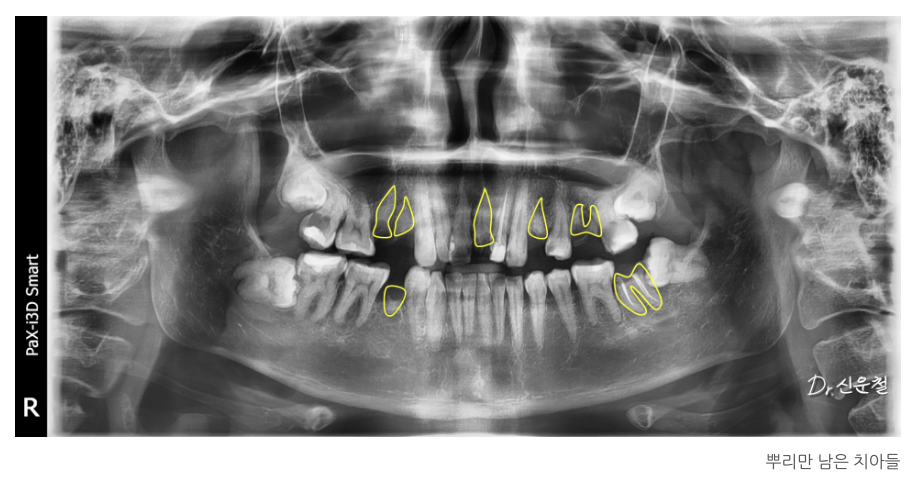

진단 결과

여러 부위의 충치와 결손치,

그리고 임플란트가 필요한 부위가 확인되었습니다.

1차 치료: 뿌리만 남은 치아 발치 (진정요법 + 무통마취 병행)